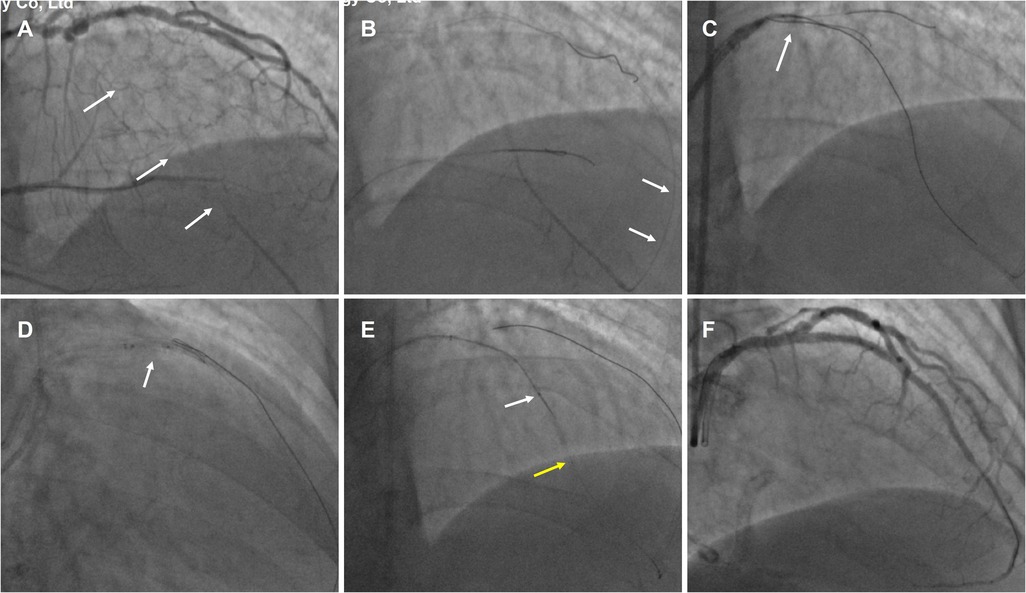

An example of the WHTH between two MCs over a long distance in Figure 2.

A 69-year-old male was readmitted for secondary PCI for LAD-CTO with significant anterior wall ischemia on SPECT tests. Diagnostic CAG showed the mid-LAD CTO after giving off the big first diagonal (D1) vessel, and with ambiguous entry, and distal LAD flow filled by apical epicardial collateral channels (CCs) from the proximal diagonal branch vessels (

Figure 2A,

Supplementary Video S1). IVUS indicated diffuse calcification with aneurysmal dilation in the proximal segment of LAD, and the CTO entrance was unclear. Therefore, retrograde approach was first attempted; Suoh 03 (Asahi Intecc) wire was advanced over 150 mm Finecross MC (Terumo Corporation) MC through the ipsilateral CC into the distal LAD (

Figure 2B). Then the UB3 wire was manipulated into the CTO lesion up to the proximal CTO cap. Due to the angulation, the wire could not enter the antegrade GC (

Figure 2C), and the retrograde MC was also unable to cross the CTO lesion. Subsequently, the antegrade Gaia 3 wire within the Corsair catheter (Asahi Intecc) was inserted into the supposed proximal cap but deviated from the retrograde wire. After performing the reverse CART technique, the retrograde UB3 wire was manipulated into the antegrade extension catheter (

Figure 2D). However, the retrograde MC was still unable to cross the CTO segment even with conventional balloon anchoring in the antegrade GC. Then, the tip-in technique was performed successfully. Unexpectedly, the antegrade MC advancement over the retrograde wire failed to cross the CTO lesion, and there was still approximately a 15 mm gap between the two MCs even when they were positioned as closely as possible. Subsequently, the antegrade guidewire was pushed smoothly while the retrograde guidewire was pulled simultaneously in a hand in hand manner until the antegrade wire entered the retrograde MC (

Figure 2E,

Supplementary Video S2). The IVUS confirmed that the wire was located in the subintimal space beyond the D1 vessel and revealed evidence of severe localized calcification in the LAD CTO. Excellent angiographic results were achieved after the drug eluting stens (DESs) implantation (

Figure 2F).

An example of the WHTH between two MCs over a long distance. (A) mid-LAD CTO (white arrow) after the big first diagonal (D1) vessel and with ambiguous entry. (B) Retrograde Suoh 03 wire was advanced through the ipsilateral CC (white arrow) into the distal LAD. (C) the retrograde UB3 wire (white arrow) crossed the CTO segment but could not enter the antegrade GC. (D) After performing the reverse CART technique (white arrow), the retrograde UB3 wire into the antegrade extension catheter. (E) WHIH technique preformed when antegrade MC (white arrow) and retrograde MC (yellow arrow) uncrossable CTO lesion. (F) Excellent angiographic results were achieved after the DESs implantation.